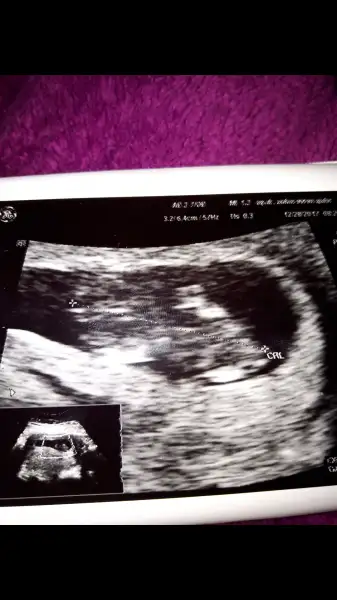

kızlar bidebenim bebegime bakın doktorum pazartesi günü erkeğe benzetmisti. Ama eminde olamayiz dedi sizde yorum yapin..

@GurbetGuzeli canım sende anliyosun bi bakarmısın

Işte burda

Eklentiler

• Screenshot_20171228-101645.webp

16,6 KB · Görüntüleme: 76

• Screenshot_20180103-121037.webp

9,2 KB · Görüntüleme: 66

Kiz gibi canim ama nerden anladin dersen erkek cocugunun vucudu daha netlesir erken zamanda ama tabi bu ultrasonun kalitesinde bagli daha kucuk tatlim bizimkiler ayniyizz bakalim ne cikcak bebisler